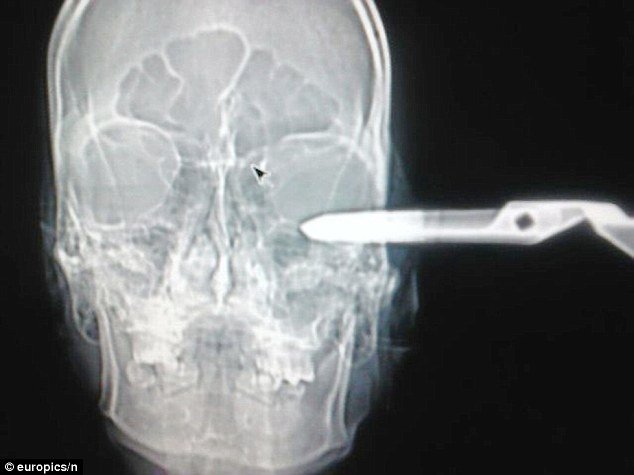

Ένας άνδρας με καρφωμένο ψαλίδι στο μάτι, μεταφέρθηκε στο νοσοκομείο και πολύ ευγενικά δήλωσε στους γιατρούς, ότι αντιμετωπίζει ένα προβληματάκι.

Ο 32χρονος Jonas Acevedo Monroy, από το Μεξικό, με το παρατσούκλι «ο Τζέντλεμαν», το οποίο και είχε αποκτήσει χάρη στους πολύ καλούς του τρόπους, οδηγήθηκε στο νοσοκομείο με καρφωμένο ένα ψαλίδι στο μάτι, αφήνοντας άναυδους τους γιατρούς με την ψυχραιμία του και την ευγένειά του.

Με μεγάλη έκπληξη αντίκρισε το προσωπικό του νοσοκομείου τον νεαρό άνδρα, με το καρφωμένο ψαλίδι στο πρόσωπο, καθώς εκείνος ρώτησε πολύ ευγενικά τους γιατρούς αν μπορούν να τον βοηθήσουν με το μικρό πρόβλημα που αντιμετωπίζει. Στην αρχή όλοι νόμιζαν ότι πρόκειται για πλάκα, μέχρι που ο άνδρας λιποθύμησε και έπρεπε να μεταφερθεί αμέσως στα επείγοντα.

Ο φίλος του που τον συνόδεψε στο νοσοκομείο, εξήγησε στους γιατρούς, ότι ο Monroy, δέχθηκε την επίθεση από άνδρα σε μπαρ, που συχνάζουν, καθώς ο δράστης, είχε εκνευριστεί με την ευγένεια που χαρακτήριζε τον 32χρονο. Έτσι, ενώ ο Monroy τον προέτρεψε να ηρεμήσει και του πρότεινε να τον κεράσει ένα ποτό, εκείνος έβγαλε ένα ψαλίδι και του το κάρφωσε στο πρόσωπο.

Ευτυχώς ο 32χρονος, στάθηκε πολύ τυχερός, καθώς το ψαλίδι αφαιρέθηκε χωρίς να προκαλέσει ιδιαίτερες επιπλοκές, και αυτή τη στιγμή χαίρει άκρας υγείας.